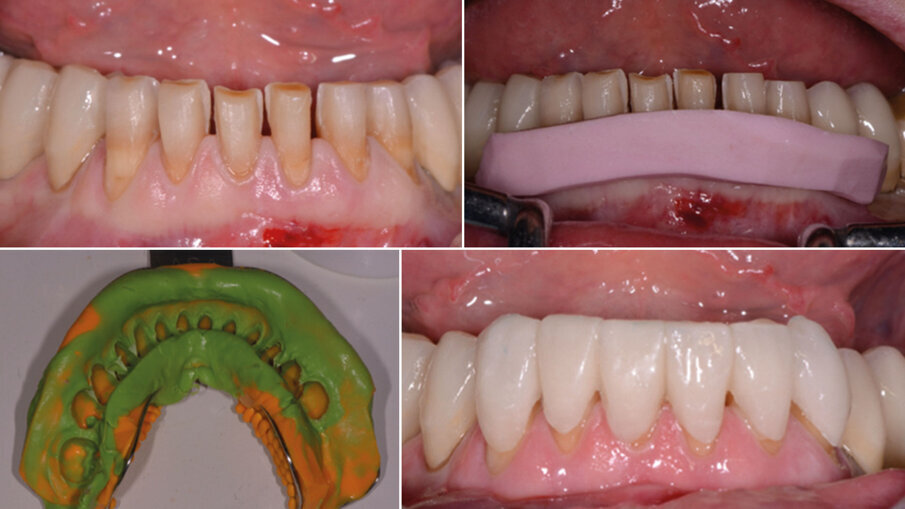

Si presenta alla nostra attenzione un paziente di 60 anni, in apparente buona salute sistemica, che ci trasferisce il desiderio di ringiovanire il suo sorriso (Fig. 1). Non affetta da patologie sistemiche pregresse o in atto, la paziente fuma più di 10 sigarette al giorno e non assume farmaci. Dopo un’attenta visita clinica, vengono prese le impronte e le registrazioni funzionali con l’arco facciale, nonché vengono scattate foto intra ed extra orali, e Opt per permettere lo studio approfondito del caso (Figg. 2, 3). Il caso viene quindi discusso insieme a tutto il team per inquadrare il miglior percorso terapeutico da proporre successivamente alla paziente in un approccio di perfetta concordance.

La riabilitazione protesica inizia con la rimozione del vecchio circolare superiore e nella ripreparazione dei monconi con sostituzione delle porzioni demineralizzate, consecutiva alla ribasatura e rifinitura dei provvisori pre limatura (Fig. 4).Per risolvere il problema estetico di mancanza di gengiva aderente attorno all’elemento 22, effettuiamo un lembo bilaminare con innesto di tessuto connettivo. Utilizzando per lo scollamento a tutto spessore nella parte centrale della recessione un inserto piezo surgery mectron apposito, solleviamo delicatamente il nostro lembo e continuiamo lo scollamento a mezzo spessore intorno al letto di innesto con bisturi (Fig. 5). Successivamente posizioniamo l’innesto di connettivo prelevato dal palato, privato della porzione epiteliale, e suturiamo con punti di sutura staccati in 7.0 sul letto ricevente (Fig. 6).

Fig. 4 - Primo provvisorio superiore.